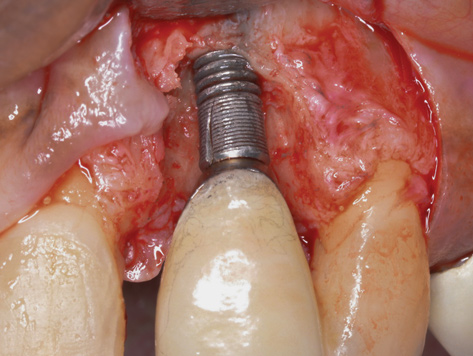

(6.) A 3.6-mm diameter implant was removed with a 4.0-mm diameter trephine drill. The apical portion of the implant was luxated carefully to preserve as much bone as possible.

Figure 6